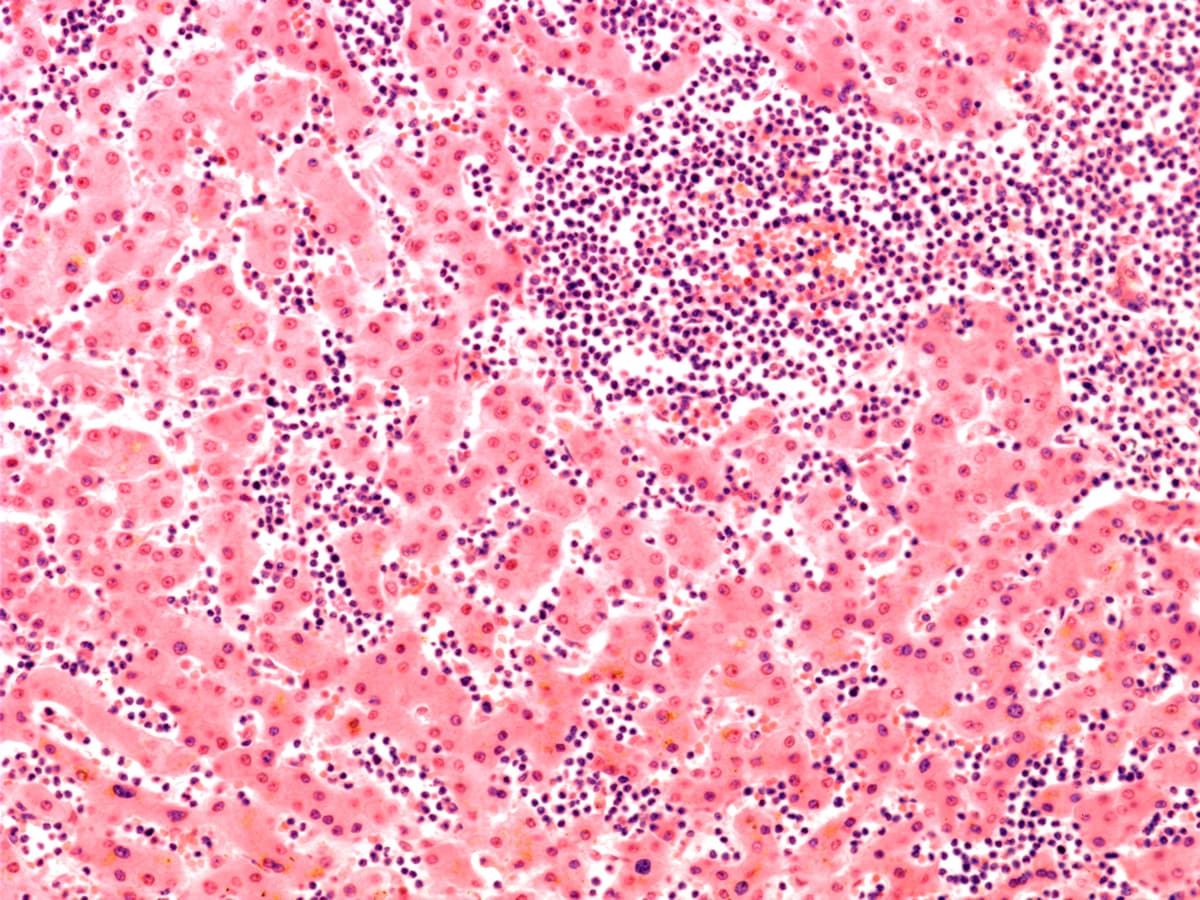

A team led by David O'Connor and Sam Behjati found that refractory T-cell acute lymphoblastic leukaemia is driven by leukaemia cells which express a key gene, ZBTB16.